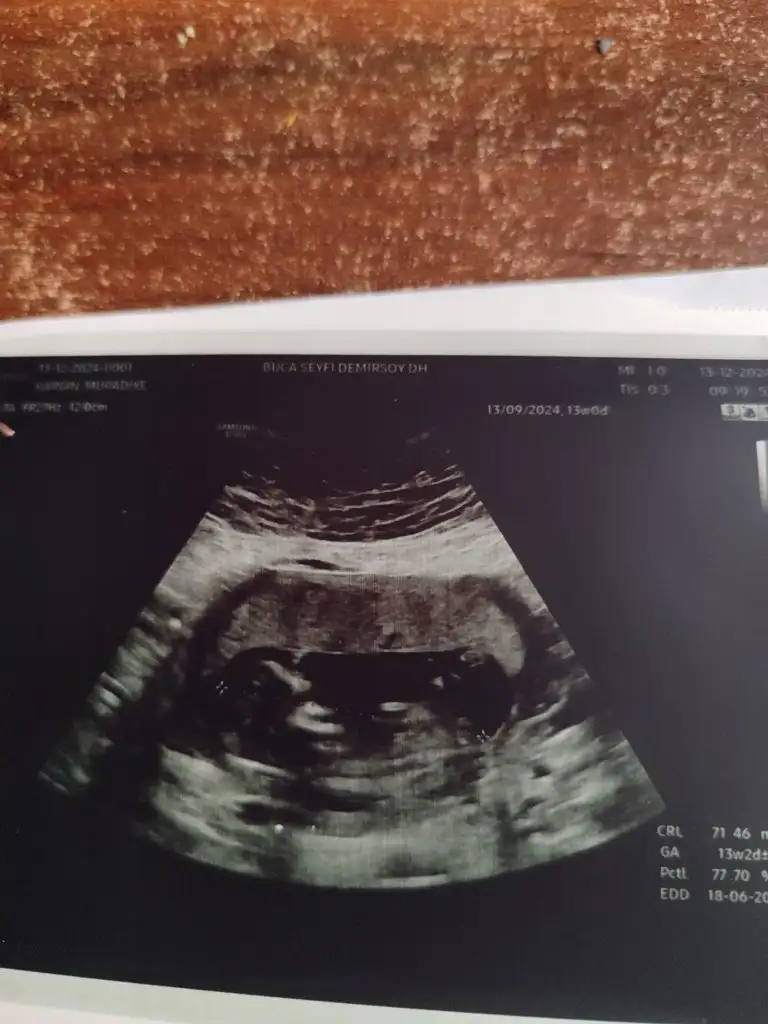

Nub a göre kız canımMerhaba, 13.hafta ultrason görüntüsüne göre cinsiyet tahmini yapabilir misiniz

Kız gibiMerhabalar.benimde tahmin edermisiniz 12+6

Pek anlamam ama kız gibi hissettimBenim için de tahminde bulunabilir misiniz lütfen![]()